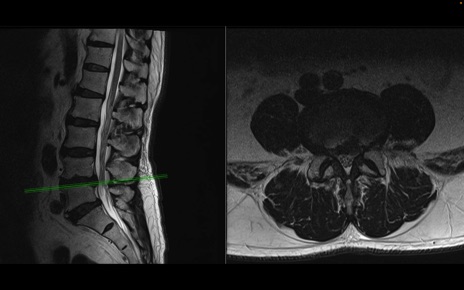

【整形】TIPS症例2 腰椎MRI 横断像と矢状断像

【症例】70歳代男性

【主訴】左下肢痛

【現病歴】2週間前くらいから腰痛、左下肢痛あり。左臀部から大腿、下腿外側のしびれが常時ある。歩行とともに同部位の痛みあり。

【身体所見】Lasegue70-/60+、Bragard-/±、PTR ±/±、ATR -/-、IP 5/5、TA 5/4、TS 5/5、EHL 右第1足趾なし/3、FHL 5/5、hypersthesia(-)、足背動脈触知良好

異常所見と診断は?